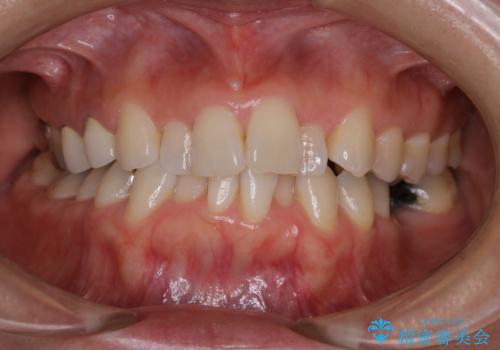

プラーク(細菌の塊)や歯石がたまると歯の表面はザラつきいてきます。そのザラつきは歯周病や虫歯菌の棲家となります。そのまま放置すると、歯肉が腫れてきたり、歯肉から出血したり、口臭が強くでたりします。とくに歯肉の境目は、歯磨きで汚れを除去することが難しく、プラーク(細菌の塊)や歯石が溜まりやすい場所です。

歯並が、がたついている場合はなおさら汚れが溜まりやすいです。矯正治療前や定期的にPMTCをすることで、矯正治療中の歯肉トラブルを防ぐことにつながります。